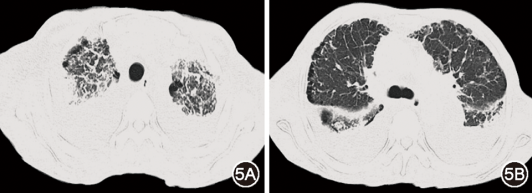

图4  腹壁脂肪活检病理:苏木精-伊红染色:淡红染无结构物质环绕脂肪细胞(图4A);刚果红染色:该物质呈橘红色(图4B);电镜:淀粉样物质呈纤维丝状,排列紊乱、僵硬,无分支(图4C);免疫电镜κ染色:κ(+++)(图4D)

患者影像学表现和全身水肿提示多部位淋巴引流不畅导致的淋巴水肿。因此入院后完善PET/CT,未发现实体肿瘤证据。筛查SPET/CT示右乳、右侧腋下及肌间多发放射性摄取增高,不除外淋巴管回流受阻所致侧支循环。因尿蛋白持续阳性(0.3 g/L),完善24 h尿蛋白2.16 g;尿蛋白电泳及定量:单克隆球蛋白82.8%;血、尿免疫固定电泳:轻链κ型单克隆球蛋白;血游离轻链:κ型3 640 mg/L(参考值范围:3.3~19.6 mg/L),κ/λ 472.727(参考值范围0.26~1.65)。结合患者多部位受累表现,考虑淀粉样变可能。后续完善骨髓涂片(图3):浆细胞占比约18%,部分细胞胞核畸形,胞体较小;骨髓活检病理:浆细胞占比约30%,结合免疫组化,符合单克隆浆细胞疾病。腹壁、舌体盲检病理:κ(+),λ(±),刚果红染色(+),偏振光下见苹果绿双折光(图4);复核我院纵隔淋巴结活检病理:渗出物中可见粉染物,刚果红(±)。系统筛查:超声心动图:左室射血分数65%,轻度主动脉瓣关闭不全,左室舒张功能减低;心脏核磁:基底段室间隔、房间隔及左右心房增厚,全心可见多发延迟强化;肌电图:双侧正中神经、胫神经损害。结合上述表现及检查,考虑系统性轻链型淀粉样变诊断明确,存在肺、纵隔淋巴结、胸膜、心脏、舌体及周围神经受累,右乳肿大考虑与淋巴回流受阻相关。